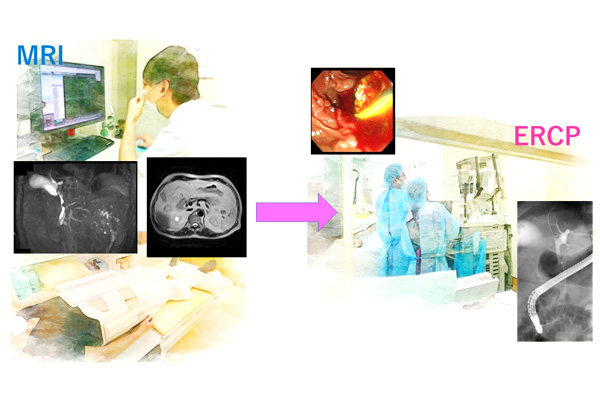

膵臓分裂は通常、磁気共鳴胆管膵管造影法(磁気MRCP)または内視鏡的逆行性胆管膵管造影法(ERCP)を使用して診断されます。

これらの方法では体内をスキャンし、医師は融合した 1 つの膵管ではなく 2 つの別々の膵管の存在を探します。

MRCP は、強力な磁場と電波を使用して、膵臓と膵管の詳細な画像を生成します。非侵襲的であり、X線を必要としません。

この検査を受ける人には、点滴によって造影剤が静脈内に投与される可能性があります。その後、被験者は、膵臓をスキャンしている間、 MRI装置内でじっと横になるように求められます。検査全体には 10 ~ 45 分かかる場合があります。

ERCP はカメラと X 線検査で、先端に小さなカメラを備えた柔軟なチューブが口から胃と小腸の上部に挿入されます。

膵臓系の X 線撮影を行う前に、医師は X 線に映る特別な色素を注射します。手続きには通常15分から90分かかります。